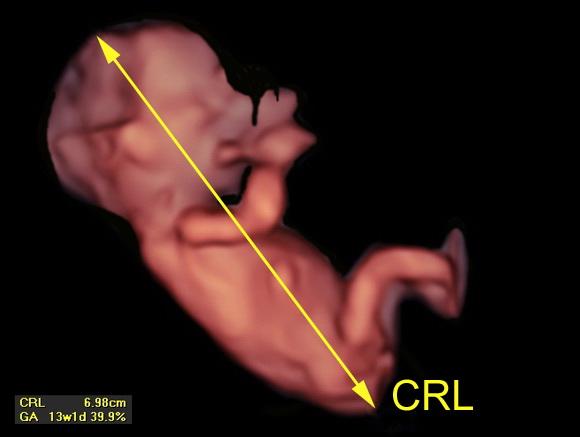

@archanjel007 toto ti odmeral aj tvoj gyn..v 12tt cca sa robi meranie crl a podla toho sa urcuje termin porodu

@nivea777 áno odmeral mi 13 týždni sme mali 8cm aj váhu mi zapísal do knižky chcela som vedieť či aj na 3d sa tomu venujú..to je cele ale už viem

@kotatko12345 sak u gynekologa áno samozrejme ved som to vysie napísala ja sa pýtam na 3d tak a u lekára ste mali koľko?